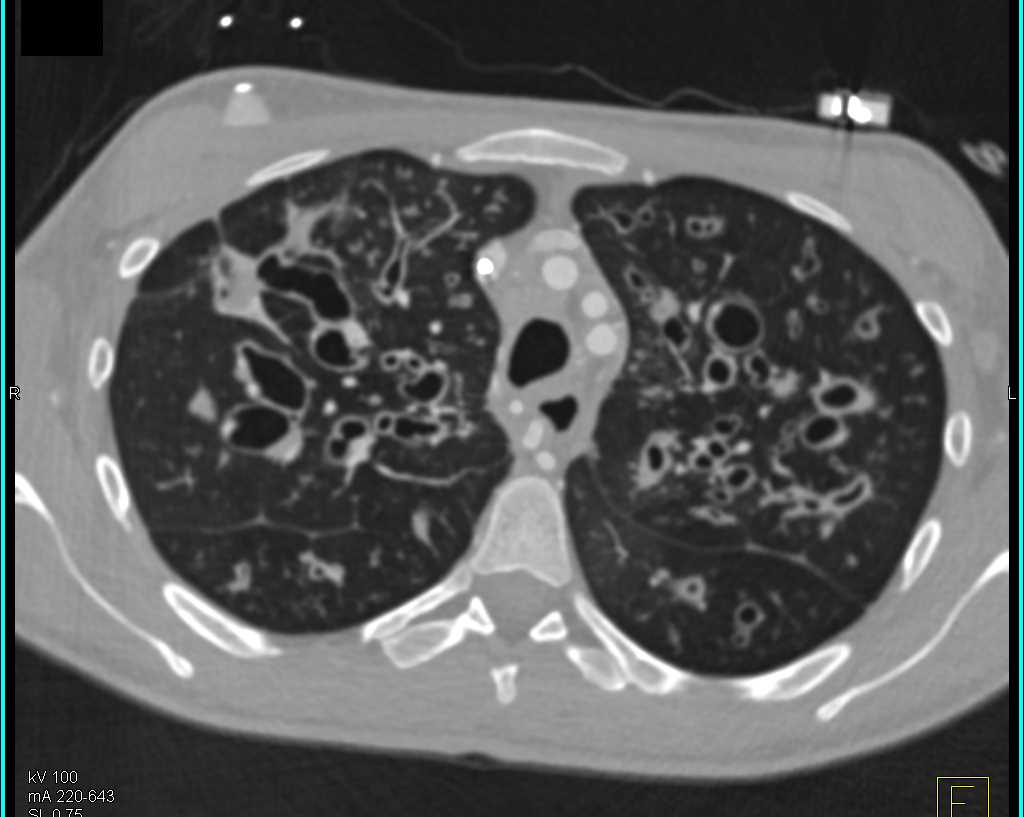

Takayasu Aortitis Involves the Left Subclavian Artery